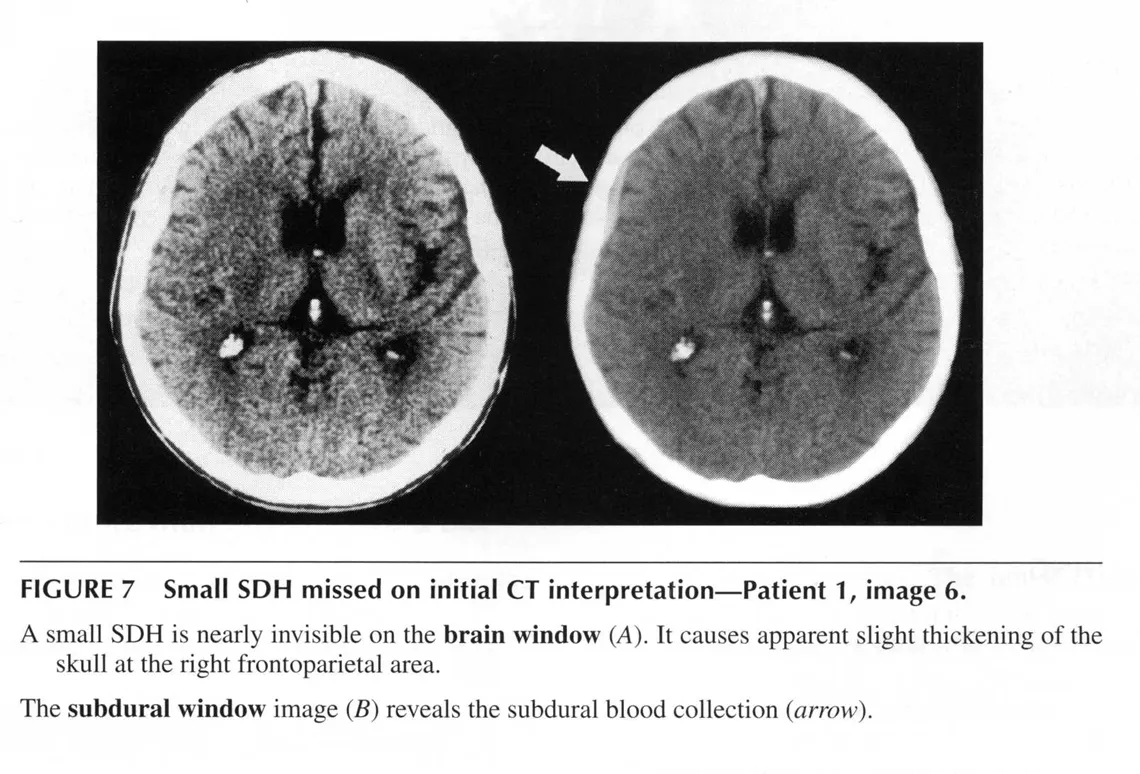

(3) Window Setting 조절 예

(해설) 아래 그림은 SDH 사례입니다. 왼쪽그림은 brain setting인데, 뇌 내 조직은 잘 구별되지만 우측 측두골에 인접하여 있는 출혈은 이 세팅에서는 뼈와 같은 정도의 흰색으로 보여 구별이 안 됩니다. 오른쪽 그림은 subdural setting입니다. 뇌 내 조직들은 각 부분을 구별하기 어려워졌지만 뼈와 혈종은 이제 밝기가 구분이 됩니다.